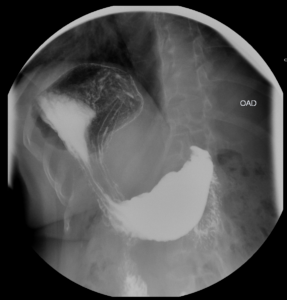

Tránsito EGD